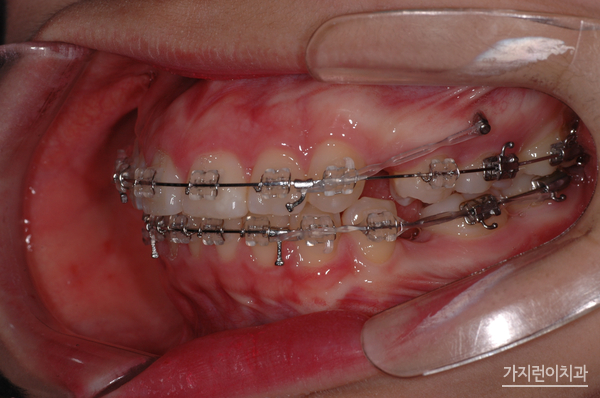

환자 분의 거미스마일과 돌출입 증상은 위 사진과 같았습니다. 치아 돌출은 물론이고 잇몸이 과도하게 나타나는 증상 때문에 스트레스를 상당히 많이 받으셨는데요. 앞으로 나온 부분을 뒤로 집어넣기 위해 상하악 양쪽의 어금니를 발치하였고

미니스크류를 식립해 상악 전치의 후방과 함입 시키는 과정을 진행했습니다. 여기서 말하는 함입과정은 상악 전치를 위로 들어올리는 과정을 말하는데요. 충분한 힘을 주기 위해 미니스크류를 식립했으며

하악에도 미니스크류를 식립해 상하악 전치가 동시에 후방으로 들어갈 수 있도록 조치를 취했습니다. 이런 교정의 과정 끝에 1년 8개월이라는 시간이 소요 되었는데요. 하지만 수술적인 방법 없이 교정만으로도 돌출입교정과 거미스마일 치아교정을 성공적으로 마쳤기에 환자분의 만족도가 높았던 과정이었습니다.